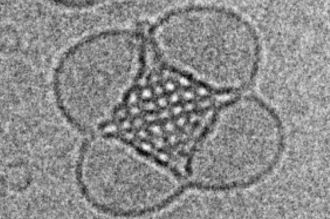

These nanoparticles have different internal structures such as layers (liposomes) or more complex 3D cubic shapes (cubosomes), with researchers discovering that these shapes have a big impact on what pathways they take to enter cells.

Cubosomes are tiny nanoscale particles formulated from the self-assembly of lipids in water. The lipids self-assemble into an intricate and complex 3D cubic structure, with water channels and lipid bridges running throughout the entire particle that can be used to package small molecule drugs.

Cubosome